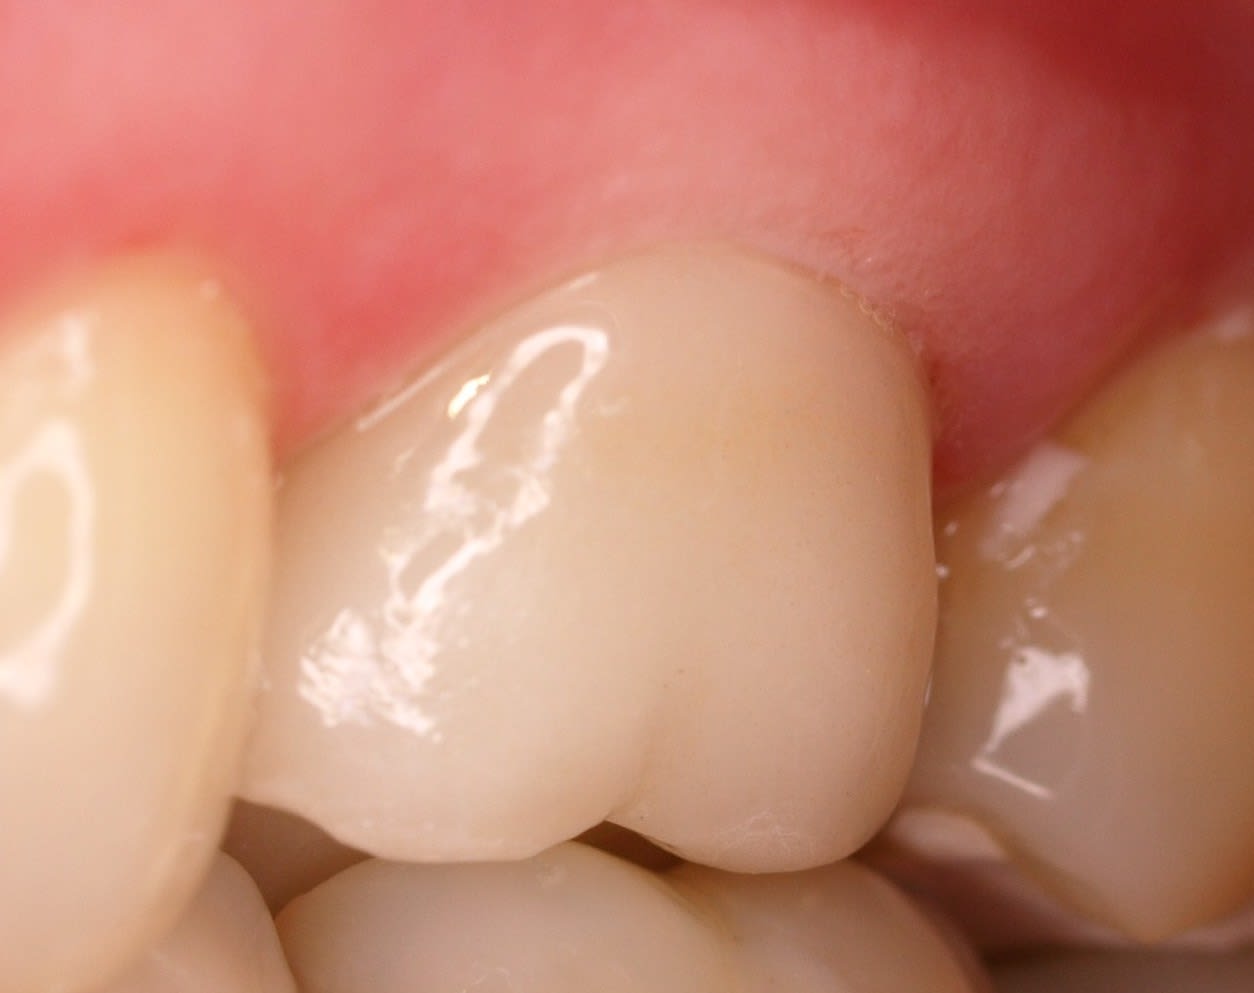

regardes la photo ,tu vois la limite , elle se trouve au dessus de la gencive . tu penses bien que le jour de la taille ,la limite paraissait plus infra .

Alors que , regarde les tailles à Chicot ,ce sont des lignes de finitions de depouille .

et bien ç est pas mal pcq tu t'en fout de la position de la taille puisque le joint est minimal et qu'en fait il a nettoyé le cement en meme temps .

il a tout explosé ,le sulcus ,la gencive et meme le debut du ligament .

au final ,il repart de neuf ,et de peu que le proto n'exploite pas le fond de la limite , il fait la couronne en retrait ,et ç est la gencive qui se reorganise EN FONCTION de la prothese . il est malin le Chicot :-)).

par contre si tu fais un congé ,ç est toi qui doit t'organiser EN FONCTION de la gencive . pas pareil .

Donc ,plus tu tailles gras et en limites horizontales , plus t'es con ou alors ç est que tu es joueur :-))

La première photo on dirais une pub pour nivea, il manque que la plume ou le bébé posé sur la gencive :)

Si tu était implanto tu ne poserais que des soft tissus level :)

En gros la meilleur façon de gérer le rapport entre la gencive et le joint prothèse dent... c'est de prendre le temps pour ne pas avoir à le gérer :)